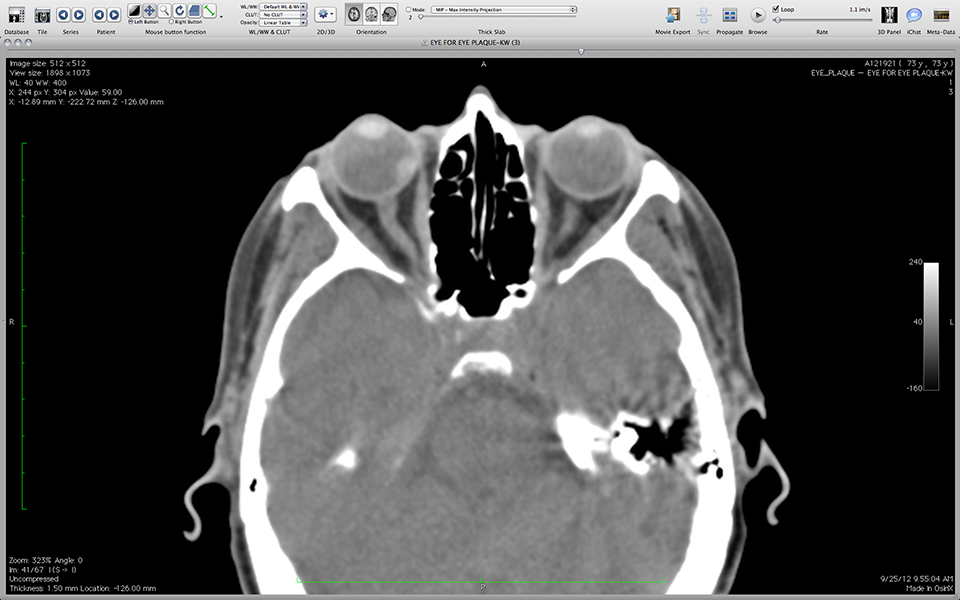

OsiriX: Opened study

OsiriXStudyOpened.png

• Navigate through the opened study using the horizontal slider located just below the title bar (EYE FOR EYE PLAQUE-KW) of the window that displays the imgages.